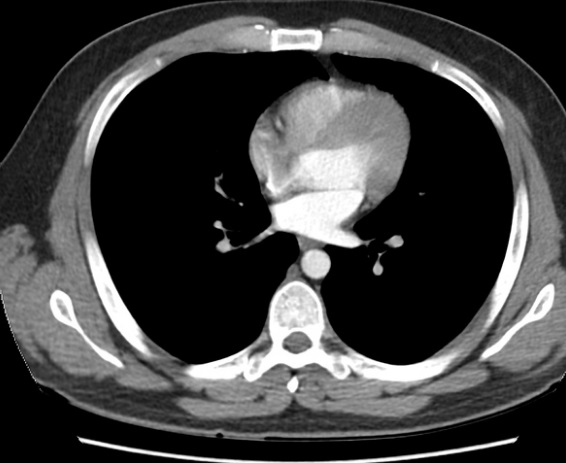

Image radiologique TDM

pulmonaire en coupe

axial avec de contrast intraveineuse . Aort

thoracique , artere , veine pulmonaire peut en vue

tres nette . |

Même cas en coupe axiale , fenetre

parenchymateuse |